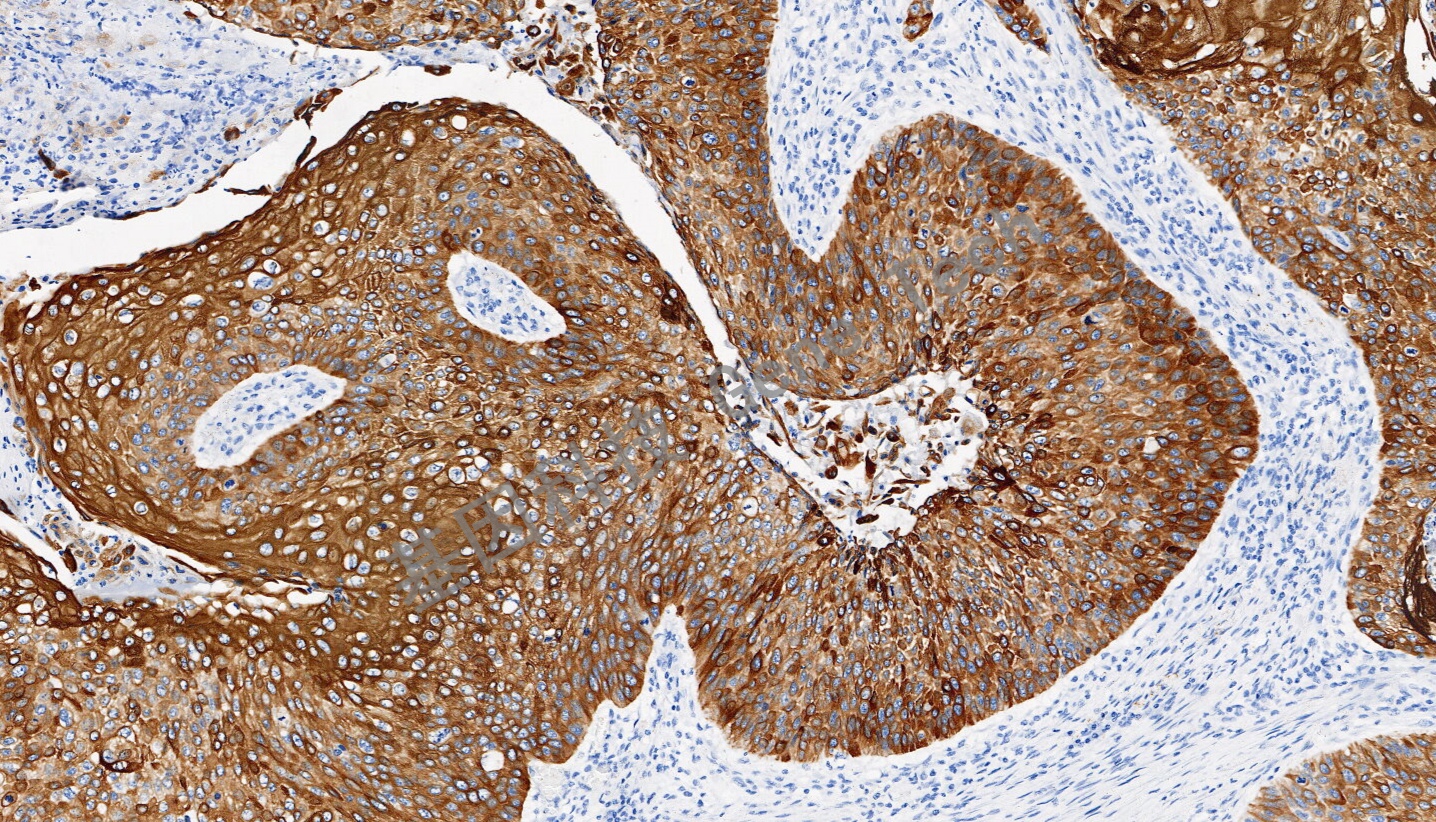

| 预处理:高pH热修复 | 阳性部位:细胞浆 | 阳性对照:食管癌 |

| 简介:细胞角蛋白6(CK6)是一种上皮特异性的II型角蛋白,通常与创伤后的角质细胞活化相关,因此也被认为是一类愈合因子。CK6总是与I型角蛋白CK16和/或CK17成对出现,通常在尚未角质化的上皮组织的基底层细胞中表达,如口腔粘膜、食道、舌乳头,在毛囊外根鞘中也有明显表达。在肿瘤组织中,CK6在多数的鳞状上皮癌中表达,特别是在鳞癌癌巢的中间成熟细胞层。CK6通常与CK5一起配套用于鳞癌与腺癌、间皮瘤与腺癌的鉴别诊断,也可用于导管上皮恶性增生的鉴别。 | ||

| 食道癌石蜡切片,用 CK6(GT2490)染色,细胞浆阳性,DAB 显色。 | ||